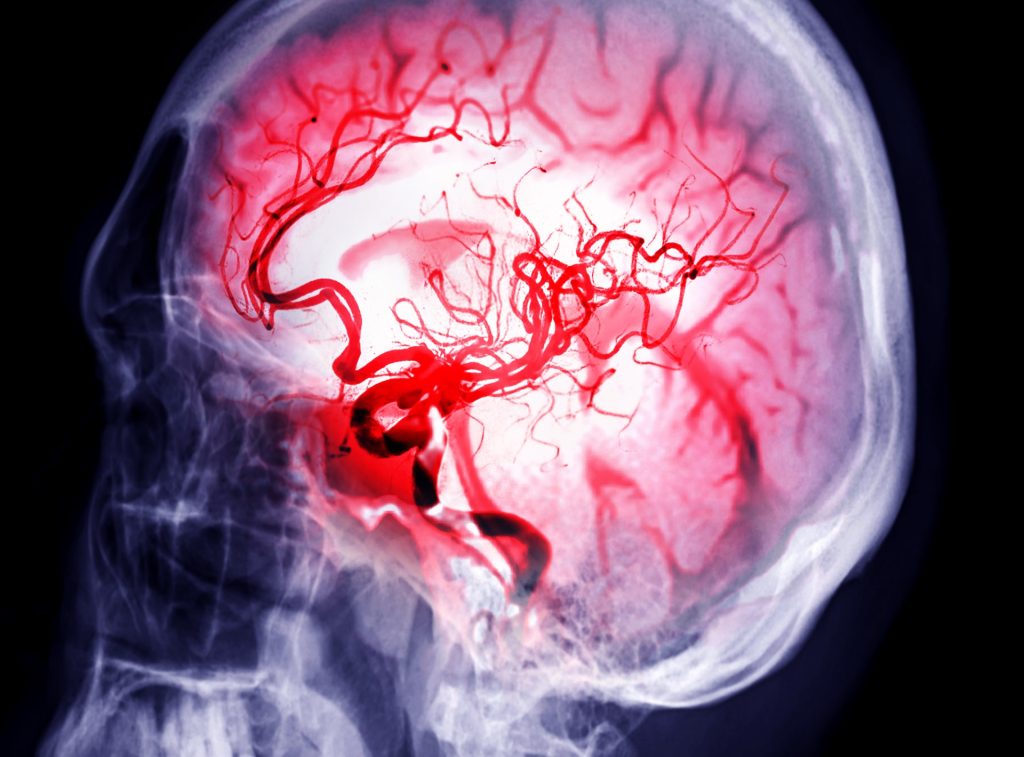

سکته مغزی یکی از اورژانسهای پزشکی حیاتی است که در آن جریان خون به بخشی از مغز قطع یا کاهش مییابد و باعث آسیب به بافت مغزی میشود. تشخیص سریع و درمان مناسب میتواند شانس بقا و بهبود عملکرد عصبی را به طور قابل توجهی افزایش دهد. در این مقاله به روشهای تشخیص، آزمایشها، درمانهای اورژانسی و توانبخشی پس از سکته مغزی و اطلاعاتی جامع درباره مراقبت و بازتوانی میپردازیم. در این مقاله به سکته مغزی و رواشهای درمان آن میپردازیم.

سی تی اسکن از مجموعهای از اشعه ایکس برای ایجاد تصویر دقیق از مغز استفاده میکند. سی تی اسکن میتواند خونریزی مغزی، سکته ایسکمیک، تومور یا سایر شرایط را نشان دهد. ممکن است ماده حاجب به جریان خون شما تزریق شود تا رگهای گردن و مغز با جزئیات بیشتر دیده شوند. این نوع آزمایش به عنوان سی تی آنژیوگرافی (CTA) شناخته میشود.

MRI از امواج رادیویی قدرتمند و میدان مغناطیسی برای ایجاد دید دقیق از مغز استفاده میکند. این آزمایش میتواند بافت مغزی آسیب دیده بر اثر سکته ایسکمیک و خونریزی مغزی را تشخیص دهد. گاهی اوقات ماده حاجب به رگ تزریق میشود تا شریانها و وریدها دیده و جریان خون برجسته گردد. این نوع آزمایش به عنوان MR آنژیوگرافی یا MR وریدوگرافی شناخته میشود.

6- آنژیوگرام مغزی

این آزمایش کمتر انجام میشود اما دید بسیار دقیقی از شریانهای مغز و گردن ارائه میدهد. یک لوله نازک و انعطافپذیر به نام کاتتر از یک برش کوچک، معمولا در کشاله ران، وارد میشود. سپس لوله را از طریق شریانهای اصلی به شریان کاروتید یا ورتبرال هدایت میکنند. بعد ماده حاجب به رگها تزریق تا شریانها تحت تصویربرداری با اشعه ایکس قابل مشاهده شوند.